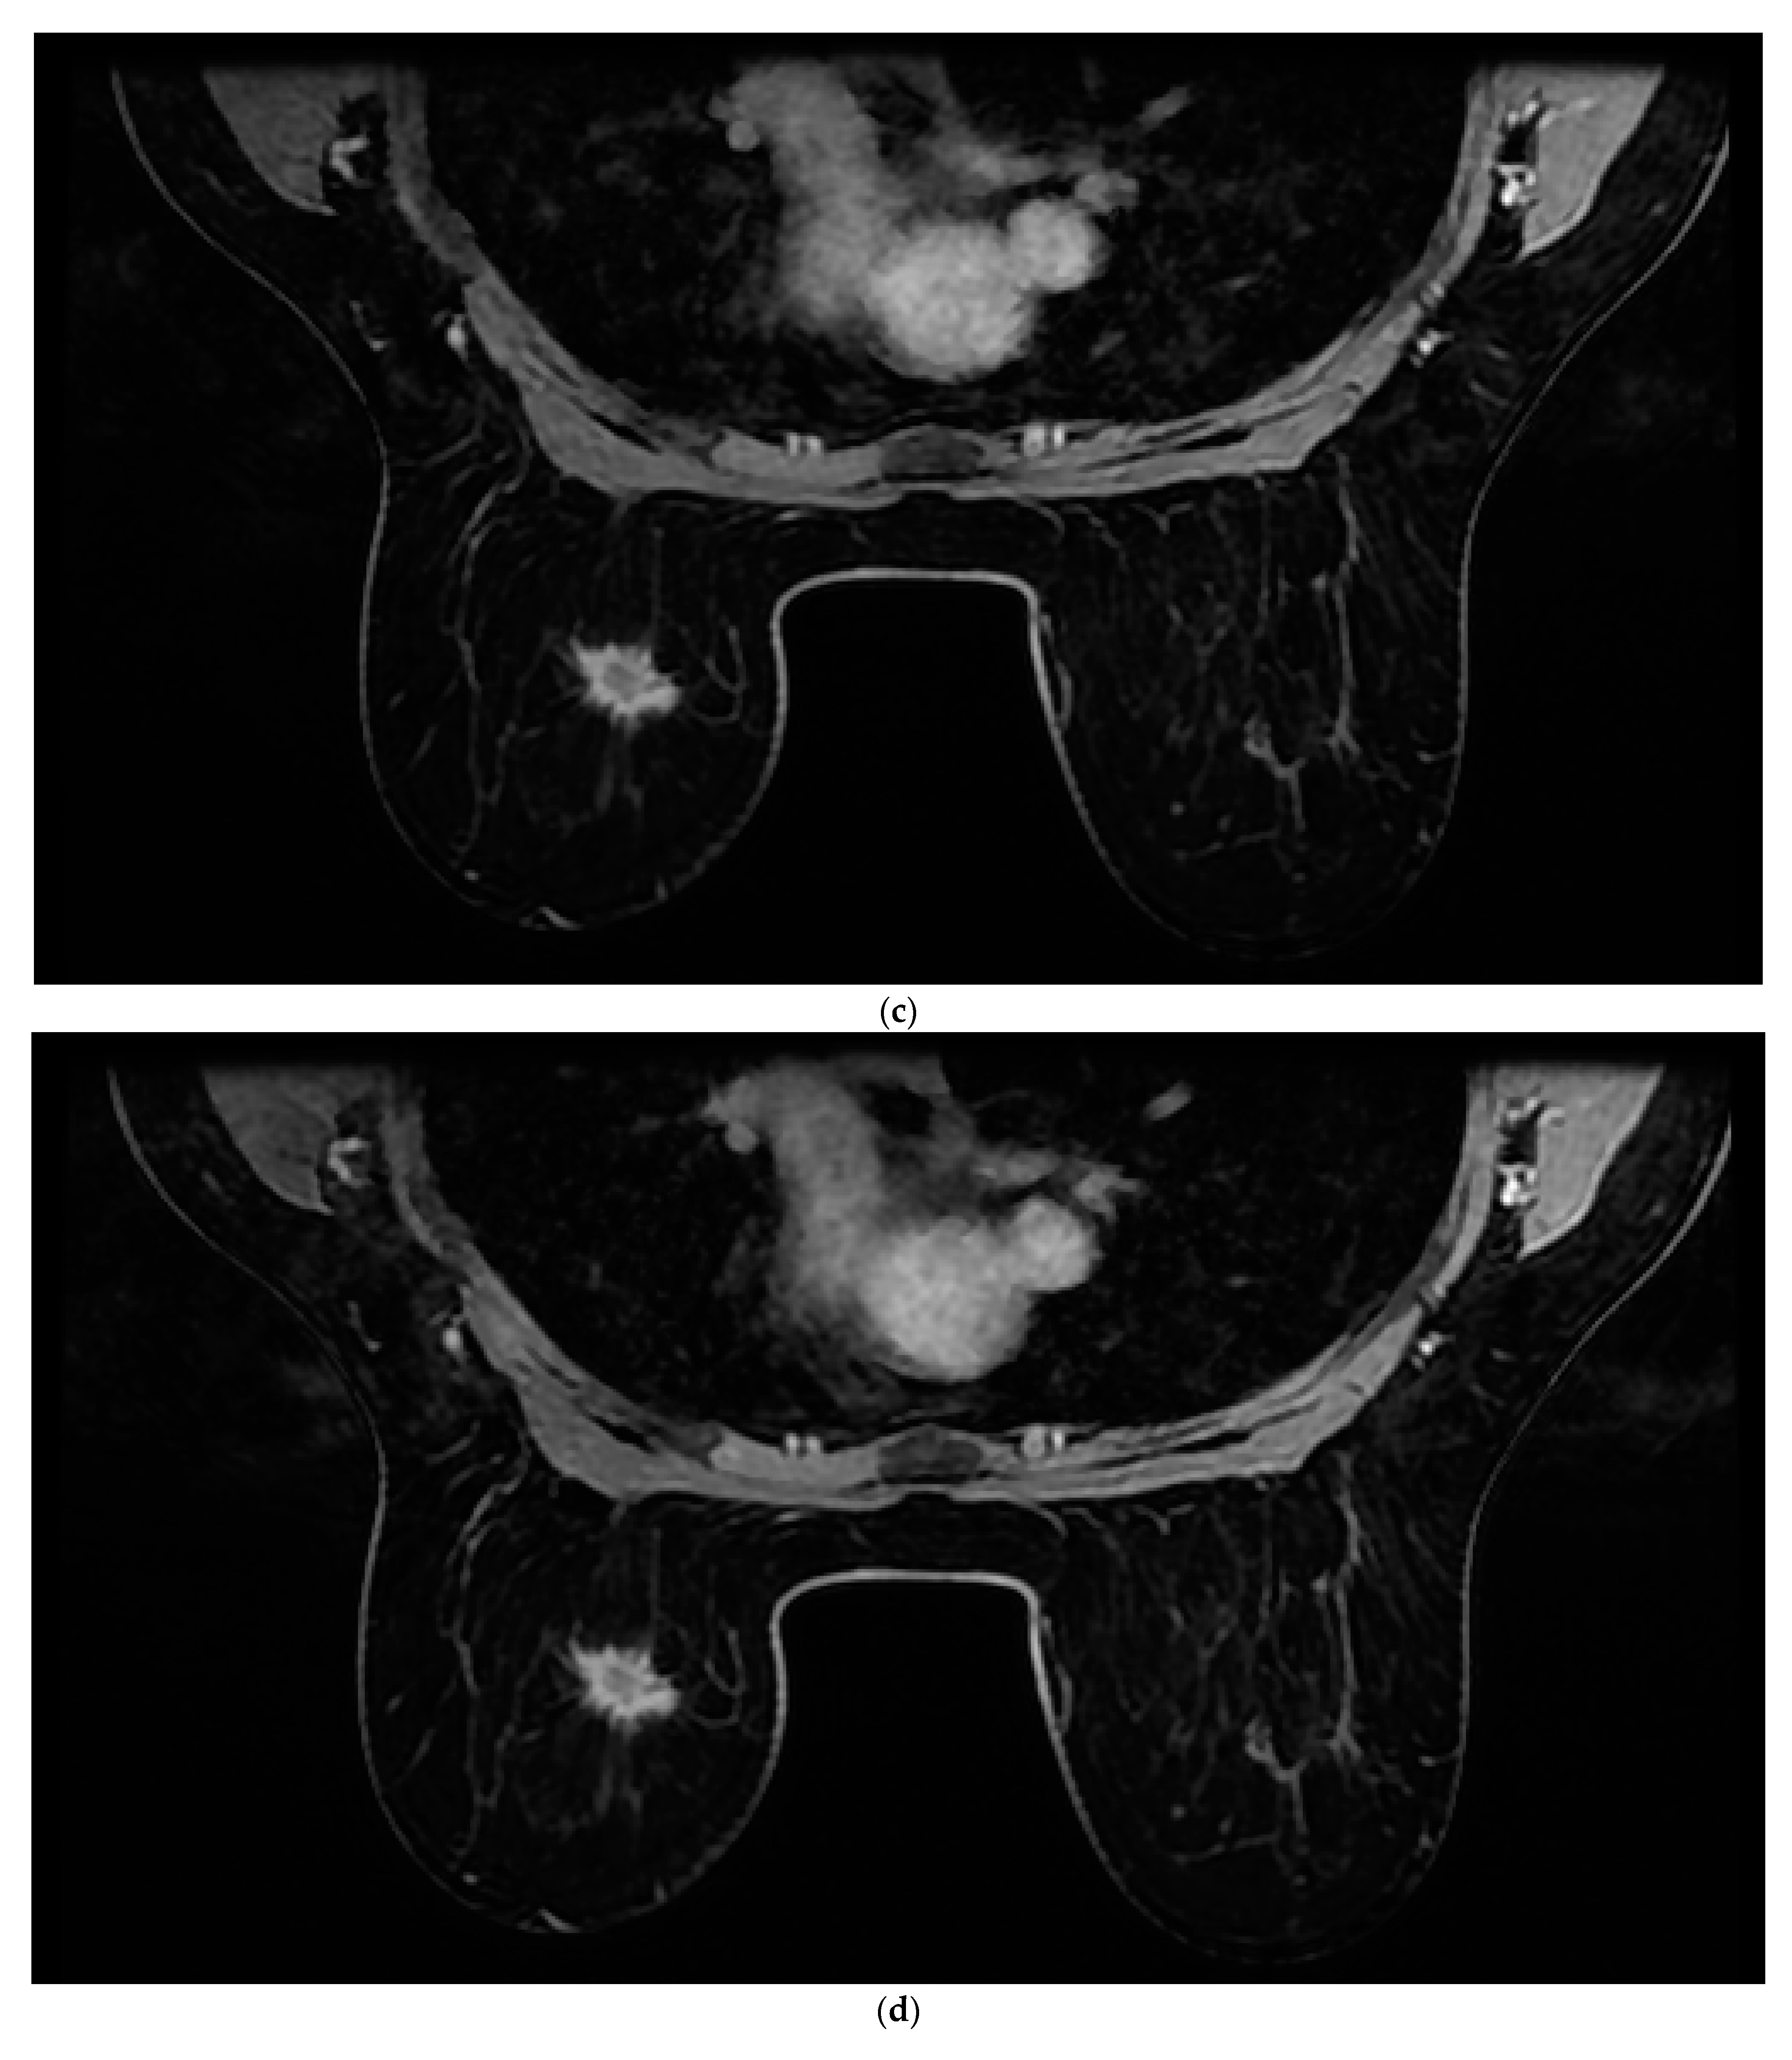

2.1. MRI and Analysis

Figure 1. Images of a 43-year-old woman with a new 2 cm left breast mass (invasive ductal carcinoma—IDC). (a) Native. (b) First postcontrast sequence. (c) Second postcontrast sequence. (d) Third postcontrast sequence. (e) Fourth postcontrast sequence. (f) Maximum intensity projection (MIP).